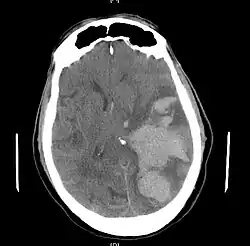

![]() | |

| MRI showing injury due to brain herniation | |

Treatment involves removal of the etiologic mass and decompressive craniectomy. Brain herniation can cause severe disability or death. In fact, when herniation is visible on a CT scan, the prognosis for a meaningful recovery of neurological function is poor.[2] The patient may become paralyzed on the same side as the lesion causing the pressure, or damage to parts of the brain caused by herniation may cause paralysis on the side opposite the lesion.[11] Damage to the midbrain, which contains the reticular activating network which regulates consciousness, will result in coma.[11] Damage to the cardio-respiratory centers in the medulla oblongata will cause respiratory arrest and (secondarily) cardiac arrest.[11] Investigation is underway regarding the use of neuroprotective agents during the prolonged post-traumatic period of brain hypersensitivity associated with the syndrome.[17]